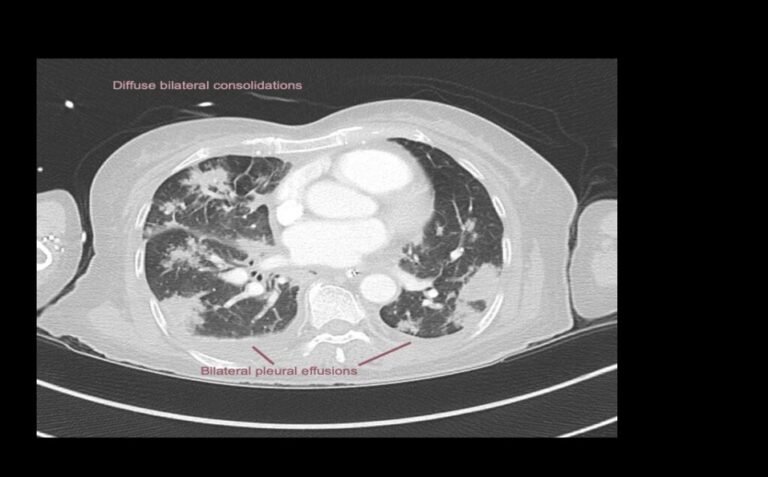

EXPLANATION -There is diffuse bilateral consolidation more prominent in the upper lobes.

There is left upper lobe cavitation. Bilaterally there are pleural effusions.